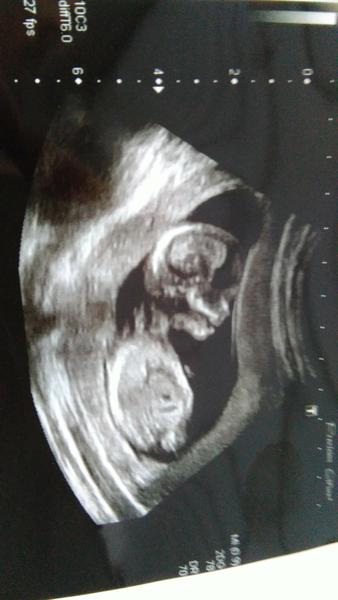

Ahojte, dnes konecne sono po mesiaci. Odlahlo mi babatinku srdiecko bilo a aj sa hybalo, som v 11+4tt, babatko ma 5,5cm a je velke akokeby som v 12+1tt. Tesim sa ze rastie. V pondelok idem ku Grochalovi, a vo stvrtok idem na usg na skrinig k svojmu dokymu. Tak snad vsetko budev poriadku a male je zdrave. A baby mam otazku, je tu niektora co ma krvnu skupinu A a rh faktor negativ ?